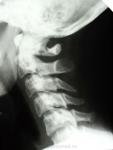

Довольно аккуратный перелом боковой массы шейного позвонка и задних дуг  антланты, наверное вданном случае обойдется все воротником Шанса, а какой механизм травмы?

такой молодой а уже хондроз..С5-6-7

а ведь остренький край С5 может и артерию поранить

Ныряльщик. Небольшое функциональное сгибание. В первый день легкий тетрапарез. В "воротнике" с поступления, сегодня вторые сутки. Рентгенография сделана вчера вечером в приемном отделении, но снимки сегодня не могу предоставить, постараюсь в понедельник.

Боковой. К сожалению, прямая проекция совершенно не информативна. Копия в начале страницы.

Да и я на рентгенограммах, кроме перелома задней дуги С1 и снижения высоты С5-6, ничего не увидела. Показала нейрохирургам, решили перебдеть, взяли на КТ. Радует, что благоприятный прогноз.